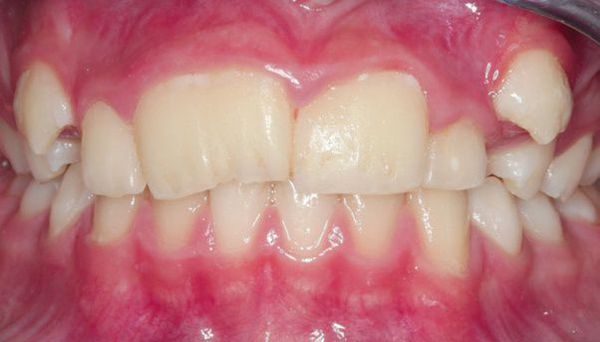

Przy mikrodoncji (microdontia) sytuacja jest odwrotna — zęby (pojedyncze lub kilka) są mniejsze niż norma, co skutkuje powstawaniem przerw między nimi (szpar, diastem). Zęby mogą mieć również stożkowaty kształt, a nadmierne odstępy wpływają na estetykę uśmiechu, fonetykę oraz prawidłowe rozłożenie sił żucia.

Makrodoncja (po lewej) i mikrodoncja (po prawej)

Niedopasowanie rozmiaru zębów do wielkości i kształtu szczęki może prowadzić do licznych zaburzeń okluzyjnych, czyli wad zgryzu (anomalii zgryzowych). Zarówno mikrodoncja (microdentia), jak i makrodoncja (macrodontia) powodują nieprawidłowe rozmieszczenie zębów w łuku zębowym i zaburzają równowagę między szczęką a żuchwą.

• Przerwy między zębami – powstawanie odstępów między siekaczami przyśrodkowymi (diastema) lub pomiędzy innymi zębami (tremy);

Głęboki zgryz na tle mikrodoncji